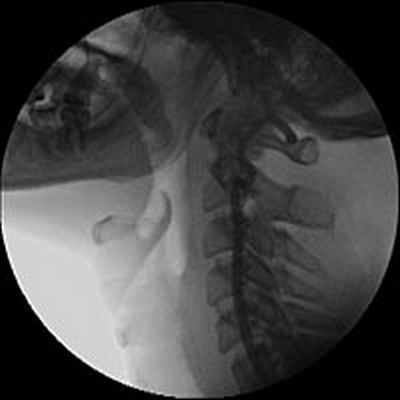

При физикальном обследовании определялось опухолевидное образование размером 6х4 см, с гладкой поверхностью, плотно-эластической консистенции, безболезненное, малоподвижное. По данным ультразвукового дуплексного сканирования внечерепных отделов брахиоцефальных артерий в левой подчелюстной области было выявлено округлое образование, в капсуле, размерами 62х41х37 мм, со слабой васкуляризацией по стенкам и в центре опухоли, не связанное с сонными артериями.

Образование принадлежит к латеральной стенке левой каротидной бифуркации и передне-латеральной стенке проксимальной порции левой внутренней сонной артерии. Также отмечалась С-образная извитость левой внутренней сонной артерии, вызванная механическим сдавлением объёмным образованием (рис.1).